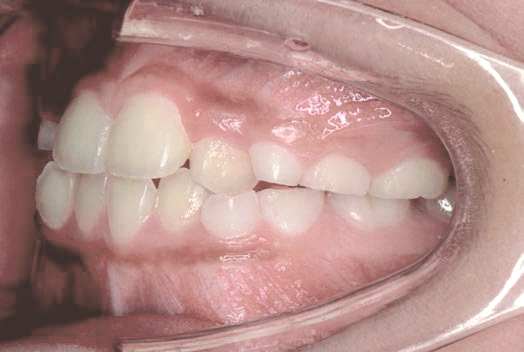

出っ歯

他院で「抜歯して5年かかる」と言われましたが、非抜歯、1年で治りました

Sさん (矯正開始時:12歳)

Before

After

下の奥歯が内側に傾いて、舌の位置が悪く、鼻がつまって口呼吸の状態でした。扁桃腺がよく腫れ、風邪をひきやすく、いびきもあるようでした。

治療を終えて

装置で上あごを拡大し、下の歯の位置を整え、前歯の並びを整えました。お口のトレーニングの効果で鼻詰まりと、いびきも改善。たった1年でこの変化が見られました。もちろん歯は1本も抜いていません。

主訴・治療内容 他院にて「抜歯した上で、ワイヤーを付け、5年かけて治療する」と言われ、他の方法はないのかとネットで調べたところ、当院を知り無料相談に来院されました。

治療期間 1年

費用 462,000円(税込)